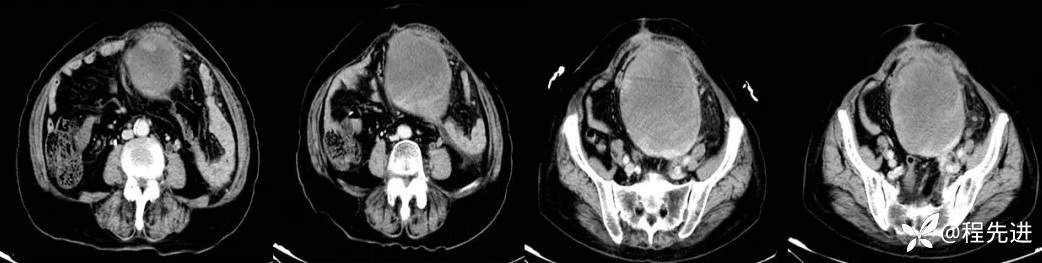

4月后患者再次腹痛半月来诊

CT平扫+增强: